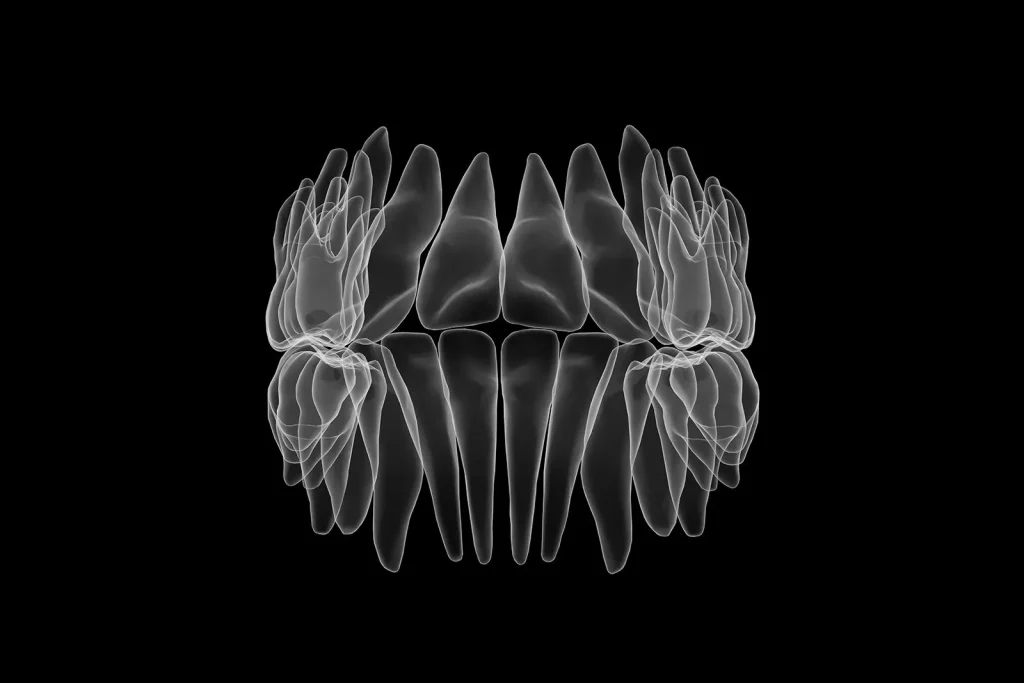

Tomografi, diş hekimleri tarafından sıklıkla kullanılan bir görüntüleme yöntemidir. Tomografi, dişlerin, çenelerin ve çevre dokuların üç boyutlu bir görüntüsünü oluşturmak için kullanılan radyolojik bir tıbbi görüntüleme yöntemidir.